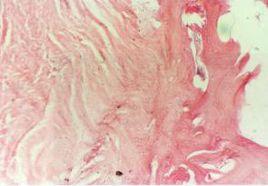

病理改變本病為骨的進行性、廣泛性和硬化性炎症,因炎性反應致骨髓腔內發生廣泛纖維化,血循環發生障礙,骨內的氧張力下降,促使骨內膜下骨樣組織增生,沉積和鈣化,haver管阻塞出現反應性骨內膜增厚,骨皮質呈梭形增生一系列病理變化。這種變化比較局限,也比較輕。和一般化膿性骨髓炎不同,它不會產生膿腫、死骨和形成瘺管。有少數傷口可能有些膿液和肉芽組織,培養可能有黃色葡萄球菌生長。